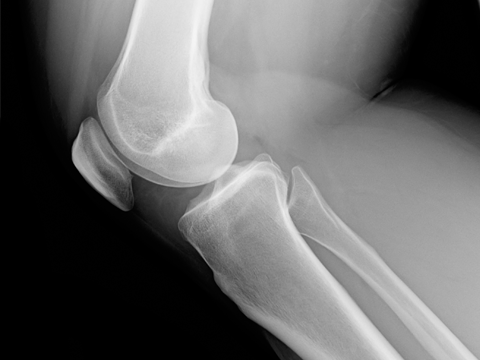

Accidentul a fost cel mai greu obstacol din viata ei. Era la Centrul Olimpic de Gimnastica de la Deva si isi menaja celalalt genunchi la care avusese o intindere. In timpul unui antrenament insa a cazut si si-a sucit genunchiul.

Miruna a fost initial tratata la Viena, unde desi medicii i-au spus ca va depasi accidentarea, durerile continuau sa apara. A venit apoi la Ponderas Academic Hospital unde medicii i-au facut investigatii imagistice detaliate. Si-au dat seama ca Miruna si-a folosit genunchiul fortat si ca, daca nu va fi operata, nu va mai putea face gimnastica niciodata.

Ce inseamna aceasta leziune: ligamentul nu se mai reface, trebuie reconstruit. Cariera Mirunei s-ar fi putut termina foarte usor aici. Dar a avut alaturi o echipa de medici care au luptat impreuna cu ea.

Miruna avea nevoie de o operatie complexa. Initial, medicul ortoped Vlad Predescu a recoltat tendoanele, le-a impletit si a creat “un siret”. Apoi a intervenit artroscopic, a construit doua tunele osoase, prin care a introdus noul ligament, pe care l-a fixat cu suruburi. Miruna a facut primii pasi inca din a doua zi dupa operatie